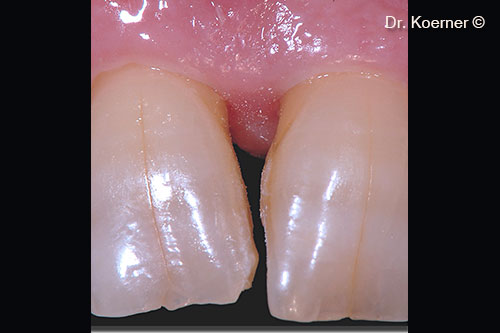

Localized periodontal defect 11